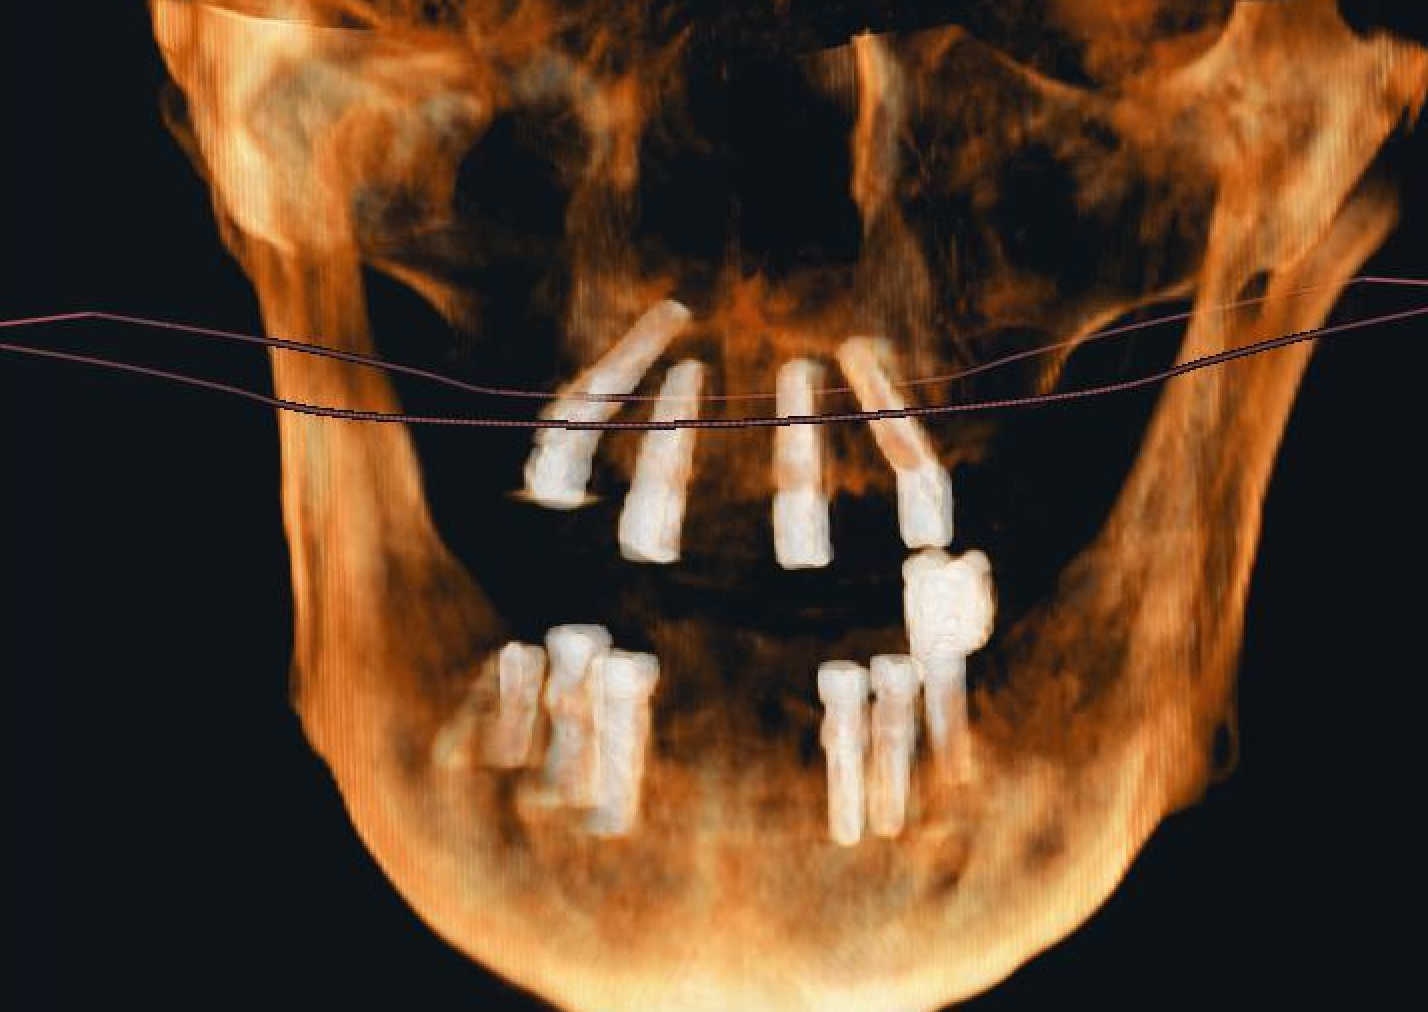

A 46-year-old male patient with severe diabetes mellitus experienced multiple tooth loss in both the upper and lower jaws. The patient also exhibited periodontal problems. Considering the patient's specific conditions, Naxis implants were chosen. Naxis implants are designed to provide better implant stability and success rates, especially in critical cases.